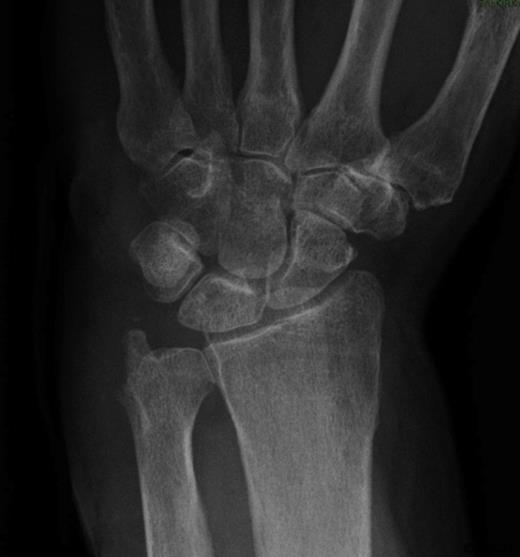

She was subsequently referred to the hand clinic. X ray this time showed destruction of the ulnar styloid consistent with a bony infection (Figure 2). MRI showed destruction localised around the ulnar head with oedematous changes extending up the shaft of the ulna (Figure 3).

MRI showing localised destruction around the ulnar head. The MRI also shows thickening around the extensor carpi ulnaris tendon in keeping with marked tenosynovitis at this site.